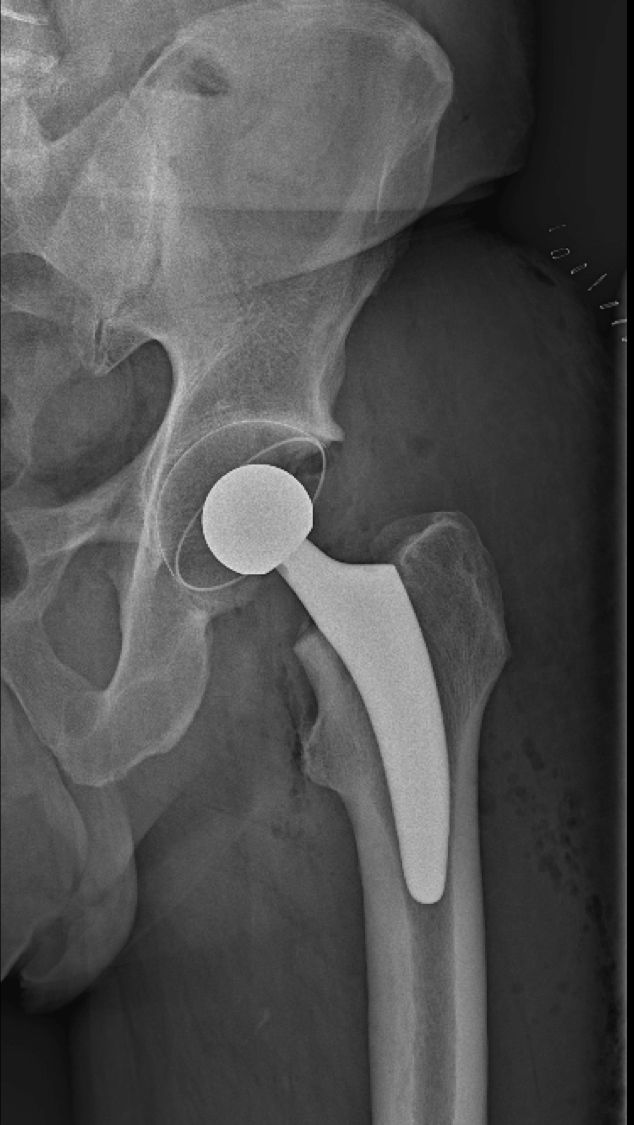

Die Hüftprothese ist zweifellos eine der erfolgreichsten orthopädischen Operationen des Jahrhunderts. Hohe Lebensqualität und lange Standzeiten des Implantates bei den meisten Patienten sind die Gründe dafür. Bei Einrissen der Gelenklippe (Labrum) oder Knochenhöcker an Pfanne oder Schenkelhals kann eventuell eine Hüftarthroskopie zielführend sein.

Ein zufriedenstellendes Ergebnis bedeutet im Hinblick auf das künstliche Hüftgelenk eine volle Wiederherstellung der Mobilität inklusive Sportfähigkeit.